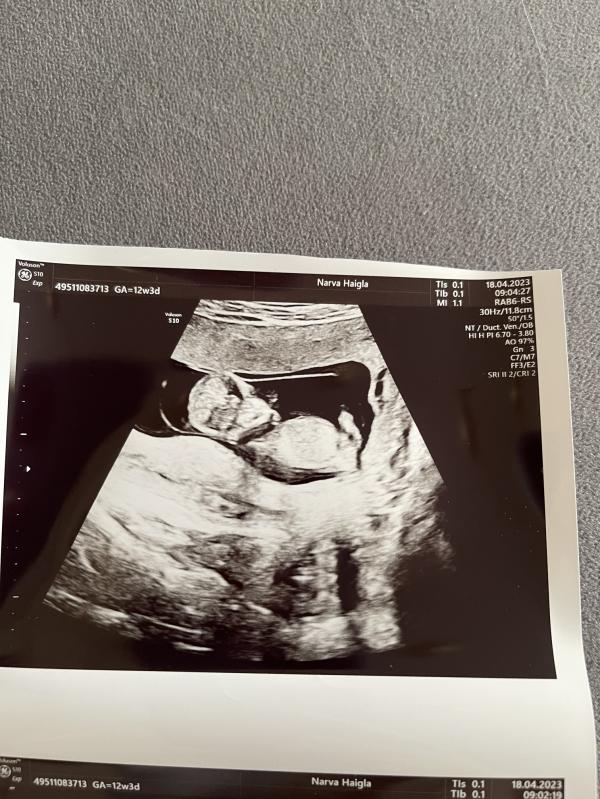

Мы тоже были сегодня на узи🥰

Развиваемся хорошо,все прекрасно работает,токсикоз пока еще есть.

Пдр-28 октября🌸